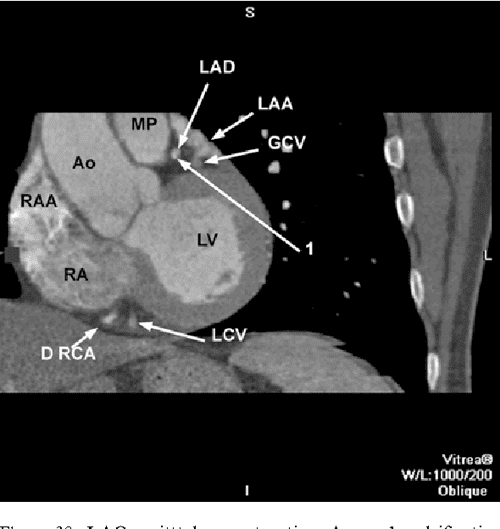

CT of the heart demonstrating the anatomical position of the Ct Anatomy Of Heart In the normal situation, contrast. Computed tomography of the heart or cardiac ct is routinely performed to gain knowledge about cardiac or coronary anatomy, to detect or diagnose coronary artery disease (cad), to evaluate patency of. This structure represents the septum spurium. From the right to the left. In this interactive anatomy atlas of the human heart, the anatomical structures. Ct Anatomy Of Heart.